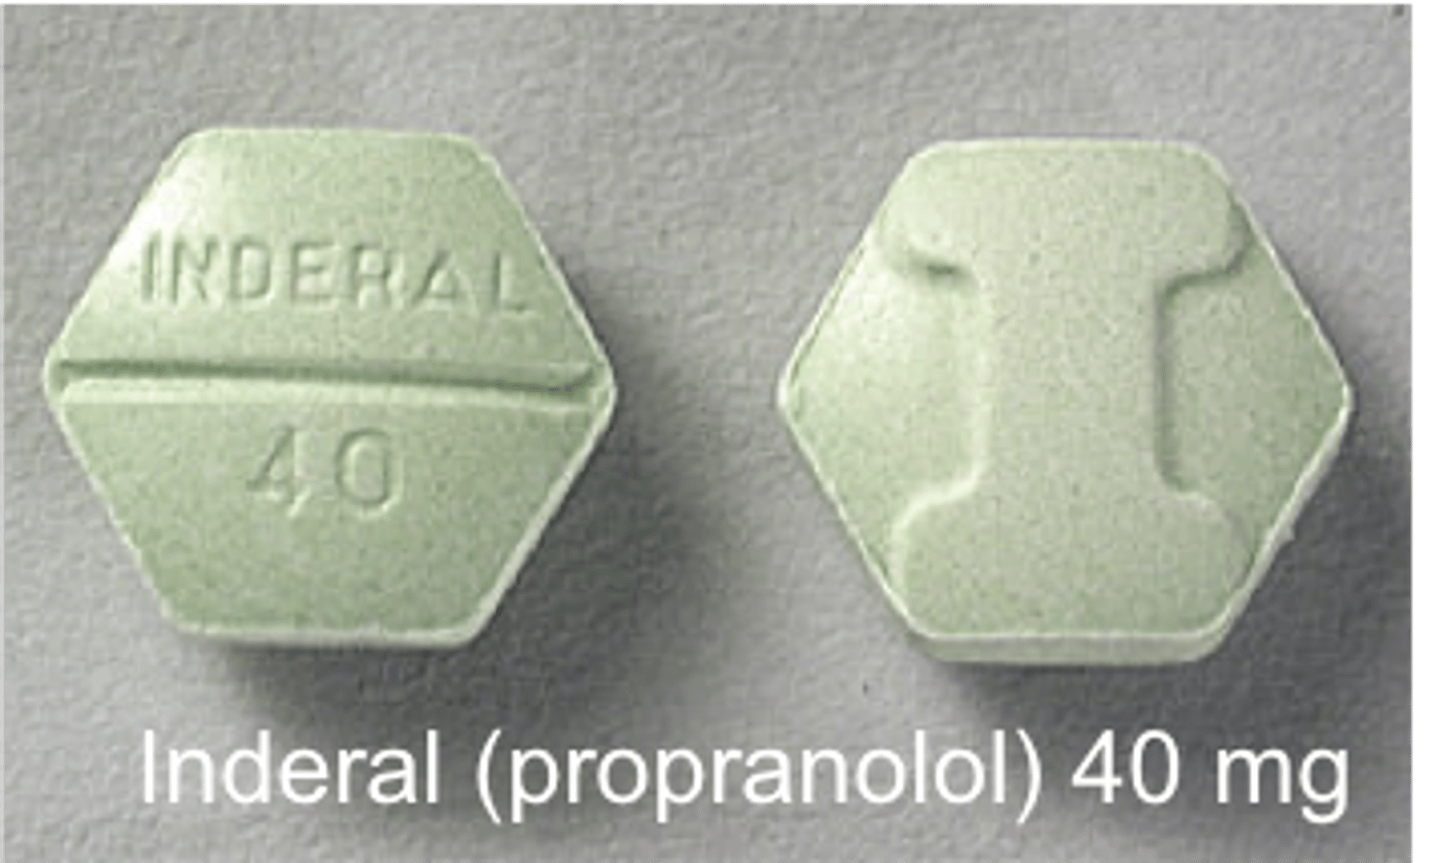

Propranolol

Brand: Inderal

Class: Beta-Blocker

Indication: Antihypertensive

Schedule: NCLM